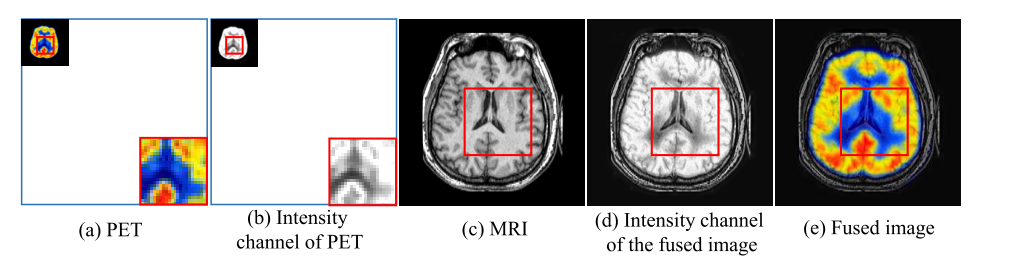

关于两种图像的介绍,原文中有大量的描写,这里我们只需要知道PET是有颜色,且分辨率低,MRI可以捕捉结构细节。

我们希望融合之后,融合图像可以保留PET的颜色信息,也可以保留MRI的结构信息。

使用IHS(强度,色调和饱和度)来表示PET图像,之类的色调和饱和度都影响颜色信息,因此我们要保持这两个分量的不变,用强度信息来与MRI图像融合。

如下图所示,可以看到PET图像的I通道(强度通道)的结构细节不够清晰,但是MRI很清晰,因此可以融合强度通道(I通道)与MRI从而弥补PET图像结构信息不足的问题。

这里PET图像的强度通道的信息保存血流之类的信息,而MRI保存软骨结构之类的信息,二者结合之后,就可以得到一个较为完整的图片信息,看到这里就感觉有点熟悉了,这个过程和我们融合红外图像很像,不同就在于红外图像提供热辐射信息,而可视图像提供细节信息。

处理过程

处理过程如下,首先将RGB图像转换为IHS表示,然后将I通道与MRI图像进行融合,再将H,和S通道进行上采样(双三次插值),将其上采样至与融合图像相同大小的分辨率,然后再将三个通道转为RGB通道,就是最后的结果。